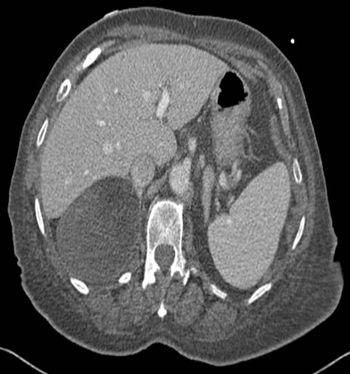

Image IQ: 67-year-old Male, Worsening Fatigue, JaundiceByDuke Duncan, MDFebruary 21st 201567-year-old male with history of worsening fatigue and jaundice.